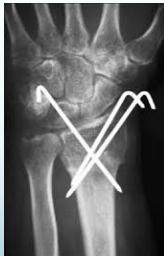

| K-wire (Kirschner Wire) | Indications: Pediatric fractures, small bone fractures in adults. Advantages: Easy to apply/remove. Disadvantages: Not stable alone, risk of infection. | , , , , , ![]() |